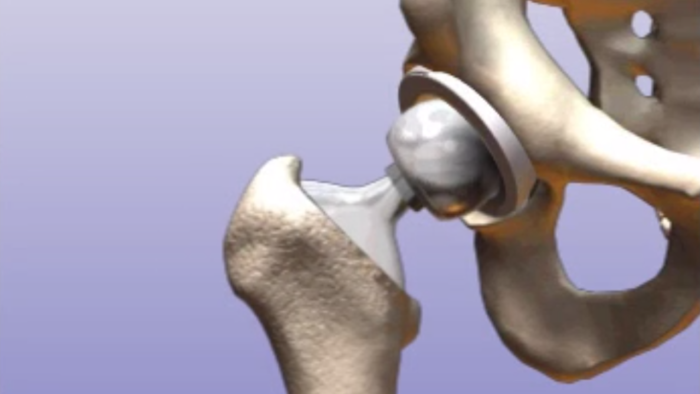

Замена таз сустава

Замена таз сустава 113 фотографий